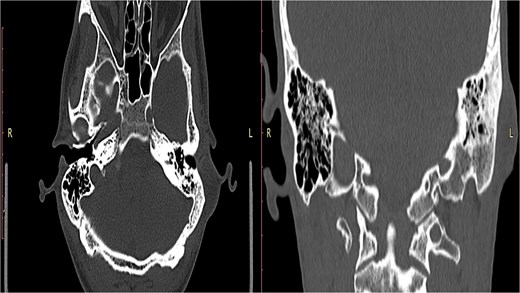

A non-contrast computed tomography (CT) scan of the head revealed a left retroauricular thickened area suggestive of either soft tissue or cystic lesion, along with left mastoid sclerosis. No definite soft tissue involvement was observed within the middle ear cavity. The ossicles were intact and in normal alignment bilaterally, and the inner ear structures, including the cochlea, semicircular canals, and internal auditory canals, appeared normal (Fig. 2).

A CT scan reveals a thickened area behind the left ear, indicating the possibility of either a soft tissue abnormality or a cystic lesion.